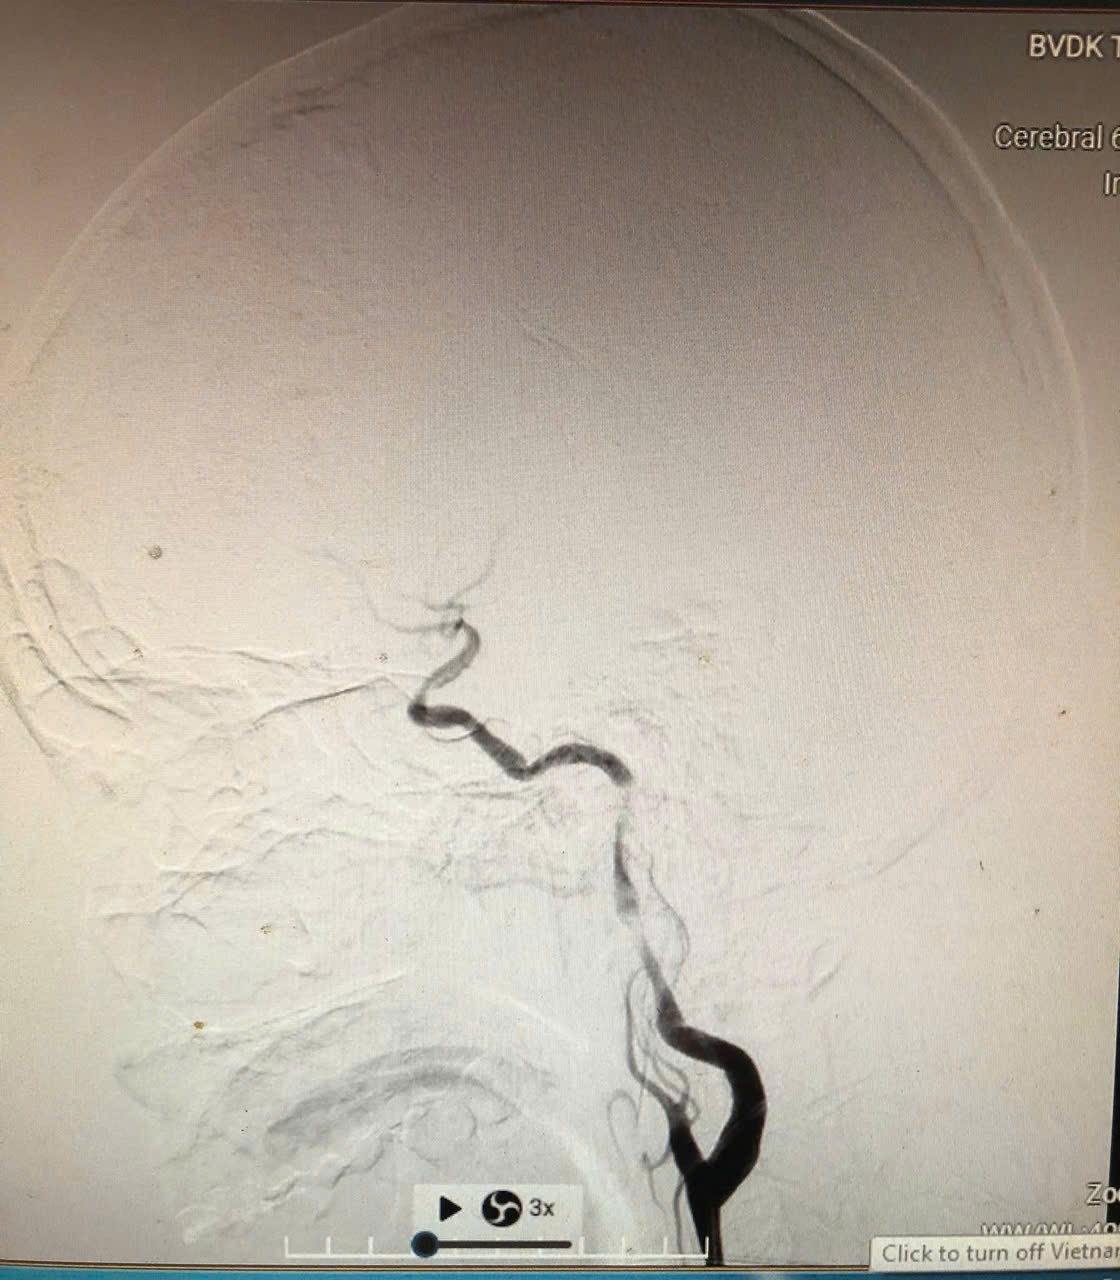

![]() |

| Hình ảnh chụp mạch máu não (DSA) trước can thiệp cho thấy động mạch cảnh trong bên trái bị hẹp nặng và tắc đoạn, dòng chảy máu lên não bị hạn chế rõ rệt |

Kết quả cho thấy, bệnh nhân bị tắc nhiều đoạn động mạch cảnh trong trái, đồng thời hẹp nặng động mạch não giữa cùng bên. Quy trình can thiệp mạch máu não được kích hoạt khẩn cấp. Trong vòng 1 giờ, các bác sĩ đã tái thông hoàn toàn động mạch cảnh, khôi phục lưu thông máu não.